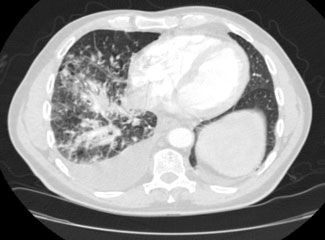

The patient was admitted with the diagnosis of right lower lobe (RLL) pneumonia on the basis of RLL consolidation on his radiograph. He was treated with intravenous ceftriaxone and azithromycin. However, there was no improvement in his symptoms despite treatment with the antibiotics; therefore, a CT scan of the chest was obtained. It revealed emphysema and mediastinal lymphadenopathy in the pretracheal and subcarinal locations (Figure 1). A moderate right-sided pleural effusion and multiple nodular opacities (measuring less than 1 cm) in right middle and lower lobes with septal thickening were noted, suggesting a lymphangitic tumor (Figure 2).